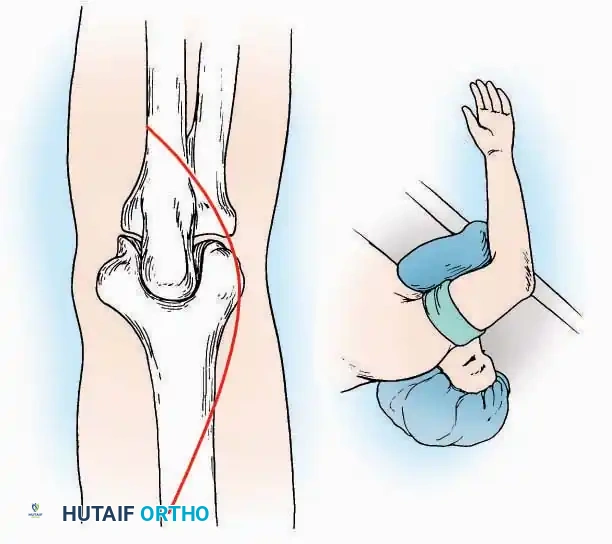

Lateral Approach (Extensile Lateral)

This is the workhorse approach for open reduction and internal fixation (ORIF) of displaced intra-articular calcaneal fractures.

Indications: ORIF of calcaneus fractures, lateral wall exostectomy, subtalar arthrodesis.

Positioning: Lateral decubitus with the operative leg up, or supine with a large bump under the ipsilateral hip to internally rotate the leg.

Surgical Technique:

* Incision: Begin the incision on the lateral margin of the Achilles tendon near its insertion. Extend it distally to a point 4 cm inferior and 2.5 cm anterior to the lateral malleolus. (For trauma, a classic L-shaped extensile incision is often used, dropping straight down anterior to the Achilles, then curving gently toward the base of the 5th metatarsal).

Medial Approach

Indications: Fixation of sustentaculum tali fractures, medial process fractures, or excision of medial tarsal coalitions.

Positioning: Supine with the hip externally rotated and knee flexed (figure-of-four position).

Surgical Technique:

* Incision: Begin 2.5 cm anterior and 4 cm inferior to the medial malleolus. Carry it posteriorly along the medial surface of the foot toward the Achilles tendon.